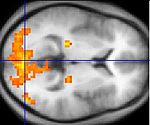

Images of the brain recorded with PET (top) and fMRI (bottom). In the PET image, the red areas are the most active. In the fMRI image, the yellowest areas are the areas that show the greatest difference in activation between two tasks (watching a moving stimulus, versus watching a black screen).

In addition to PET and fMRI, which show which areas of the brain are activated by certain tasks, researchers also use diffusion tensor imaging (DTI), which shows the neural pathways that connect different brain areas,[31] thus providing insight into how different areas interact. Functional near-infrared spectroscopy (fNIRS) is another hemodynamic method used in language tasks.[32]